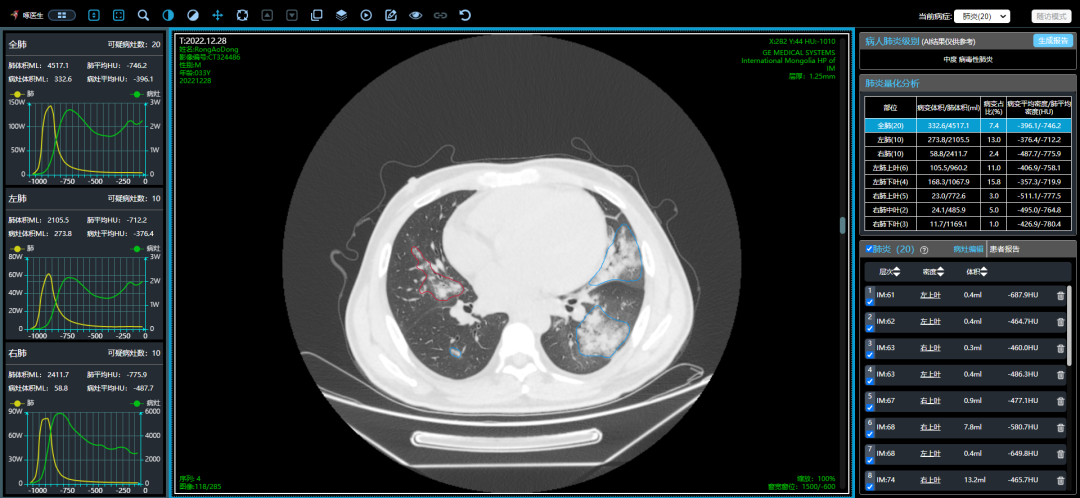

近期,多地醫(yī)生發(fā)現(xiàn)患者出現(xiàn)肺炎或白肺癥狀,引發(fā)關(guān)注。那么什么是白肺呢?其實(shí)白肺是肺部影像學(xué)表現(xiàn)的一個(gè)口語化描述。當(dāng)出現(xiàn)炎癥和感染,肺泡被滲出液等填充,在影像學(xué)上的表現(xiàn)就是出現(xiàn)白色區(qū)域。并不是只要肺部出現(xiàn)了炎癥就都叫白肺,一般來講肺部炎癥較重、滲出液較多,白色的影像區(qū)域面積達(dá)到70%?80%時(shí),在臨床上把它稱為白肺。通過“啄醫(yī)生”可以準(zhǔn)確地識別新冠肺炎的典型白肺影像,以下選取幾例最新病例加以說明。

從這3個(gè)確診新冠肺炎呈“白肺”病例來看,“白肺”多見于老人、兒童以及帶有基礎(chǔ)病的新冠患者,病灶可發(fā)生在肺內(nèi)任何肺葉,病灶形態(tài)特點(diǎn)也是多樣化,符合病毒性肺炎的影像表現(xiàn)。從影像學(xué)角度出發(fā)重點(diǎn)在于快速評估病情,提升人工讀片的客觀性。 “啄醫(yī)生閱片機(jī)器人??新冠肺炎CT影像輔助分診與評估系統(tǒng)”可以準(zhǔn)確地識別新冠肺炎的典型影像表現(xiàn)如雙肺外周胸膜下多發(fā)的磨玻璃影、小葉間隔增厚或合并鋪路石征等,對于部分患者由于影像表現(xiàn)早于臨床癥狀,更具有早期發(fā)現(xiàn)、早期診斷的優(yōu)勢。